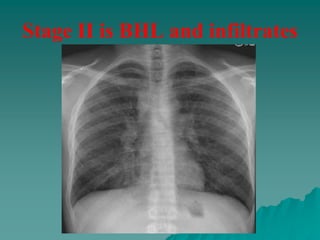

– stage 2, bilateral hilar lymphadenopathy with infiltration.

Stage II is BHL and infiltrates